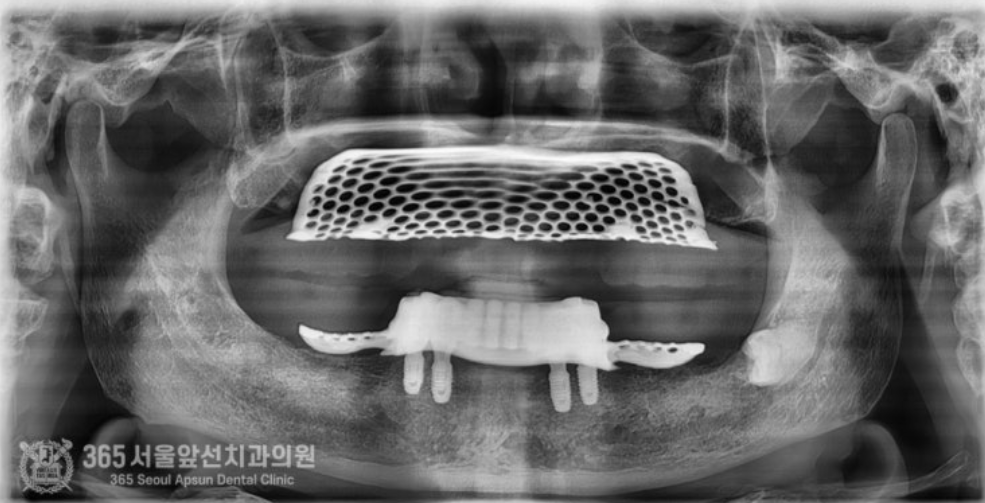

촬영일시 : 2024.08.09 완성된 임플란트 브릿지 엑스레이 사진입니다. 짱짱하게 생겼습니다 ㅎㅎ 이제 브릿지를 이용해서 위아래 틀니를 제작해줍니다. 이때 턱의 높이를 결정하고 턱의 위치를 잡아주는 과정을 거쳐 정확한 위치에 보철물을 제작하게 됩니다.

촬영일시 : 2024.09.12 모든 치료가 완료되었습니다ㅎㅎ 환자분께서는 편안한 식사를 하시게 되어 행복을 되찾으셨습니다. 앞으로 좋은 증례로 찾아뵙겠습니다. 지금까지 365일 열린 가까운 서울대학교 치과병원을 지향하는 주안역치과 365서울앞선치과였습니다. 감사합니다. 365서울앞선치과의원 블로그의 임상 케이스 게시물은 환자분께 의학적으로 정확하고 상세한 정보를 드리기 위해 각 진료과 의료진이 직접 작성하며, 모든 증례 사진은 본원 의료진이 직접 시술한 증례를 촬영한 것으로, 의료법 제23조, 제56조에 의거하며 환자분의 동의를 얻어 포스팅에 사용하였습니다. 또한 해당 케이스는 본 환자분의 치료 결과이며, 환자 상태에 따라 치료의 결과는 달라질 수 있습니다. |